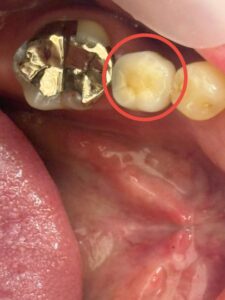

左下奥歯から1つ手前の歯が破折し、腫れや違和感が続いていたため、抜歯のうえインプラント治療をご希望されました。

破折歯を抜歯後、抜歯窩が完全に治癒するまで十分な期間を置き、その後インプラントを埋入しました。

骨量は十分にあったため、手術は約15分ほどで終了しました。

現在、経過は良好で、上部構造を装着し、しっかり噛める状態を継続していくことを目指していきます。